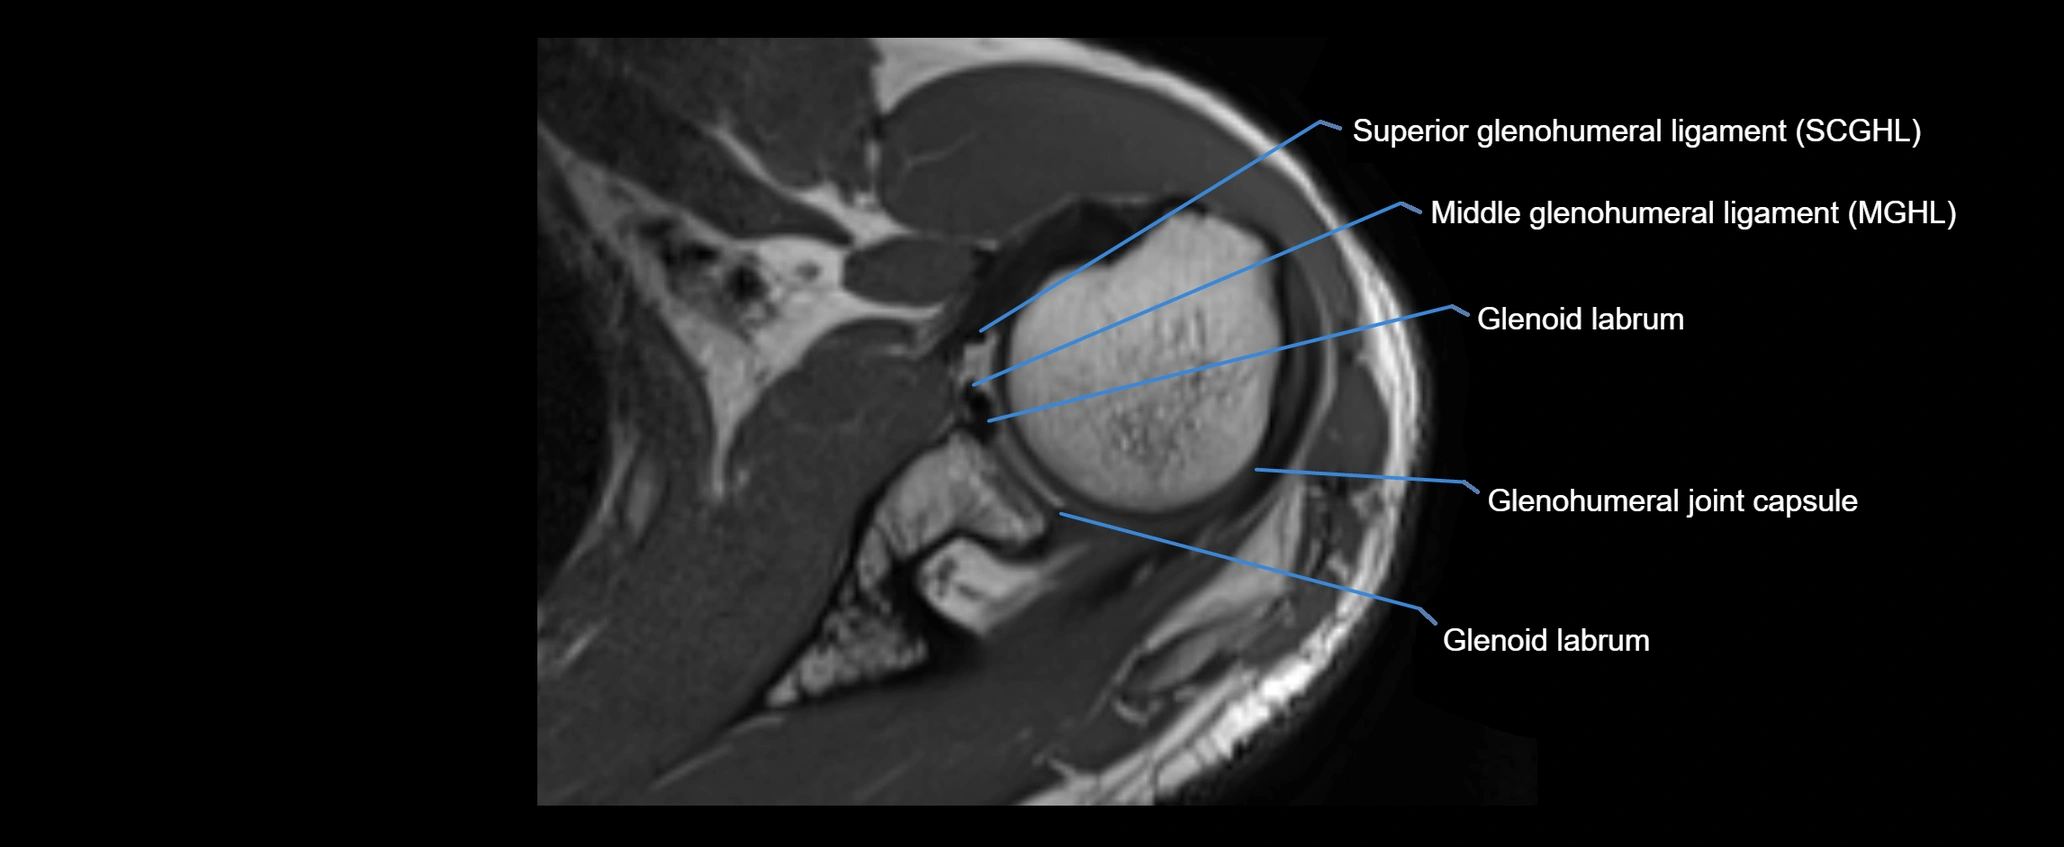

MRI images

image